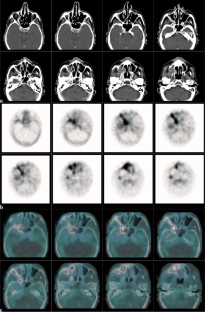

Abb. 2 a–c: